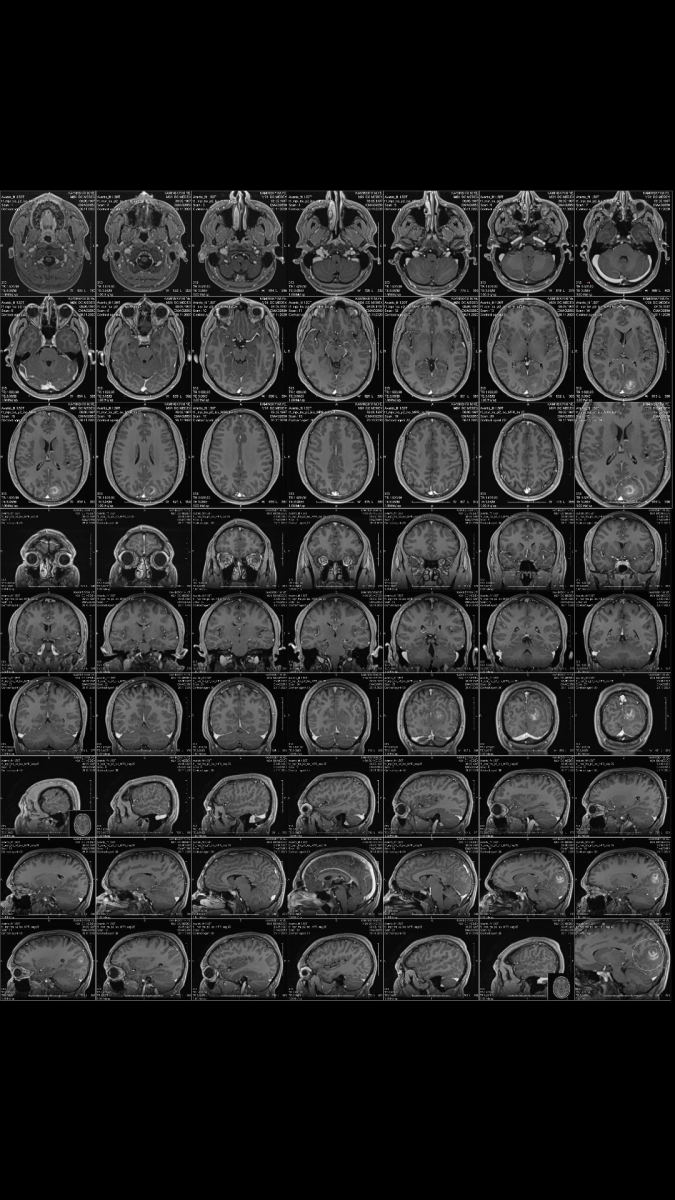

Здраствуйте прошу помощи, моему племяннику - действующему военнослужащему Морской охраны нужна срочная помощь. У парня диагностировано опухоль головного мозга. Документы прилагаю. Будем благодарны любой помощь, так как операция дорогостоящая.

Screenshot_20201128-151034.png

20201126_123205.png